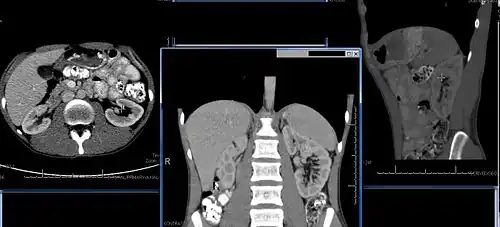

Imaging

Renal ultrasonography is essential in the diagnosis and management of kidney-related diseases.[49] Other modalities, such as CT and MRI, should always be considered as supplementary imaging modalities in the assessment of renal disease.[49]